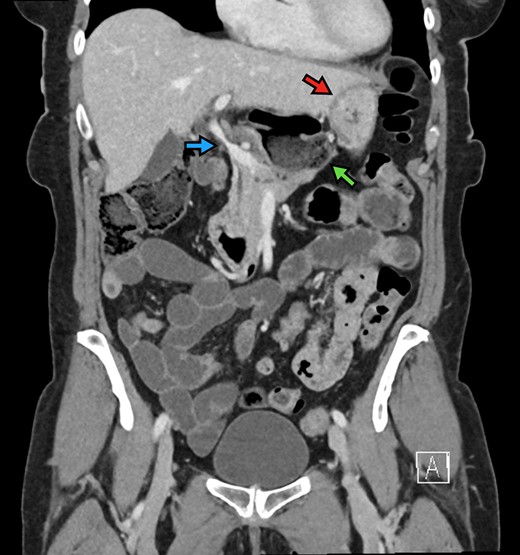

The patient is a 70-year-old woman who presented to the emergency department with acute-onset abdominal pain throughout her epigastrium for approximately 2 hours. The pain was constant and severe, extending across the bilateral upper quadrants. She had experienced pain like this once before within the past year which spontaneously resolved within 4 hours. The patient’s last oral intake was an hour before onset of the pain, and she denied any fevers, chills, nausea or vomiting. She was an otherwise healthy woman who took no medications and had no abdominal surgical history. On admission, vital signs were normal, with a heart rate in the 70’s. Although initially reported as tender by emergency department staff, after pain medication and intravenous fluids, examination by the surgical team revealed resolution of pain and a soft, non-tender abdomen. Lactic acid on presentation was 5.0 mmol/l, and her white blood cell count was 9600 µl−1, with the remainder of her laboratory values within normal limits. She underwent a computed tomography scan which demonstrated herniation of her cecum through the FoW, causing compression of the inferior vena cava (IVC) and portal vein (Figures 1–3).

The cecum is absent from the right lower quadrant and is located between the liver and stomach (red arrow) visualized as an air-fluid level (green arrow). Compression of the portal vein by herniated contents is demonstrated (blue arrow).